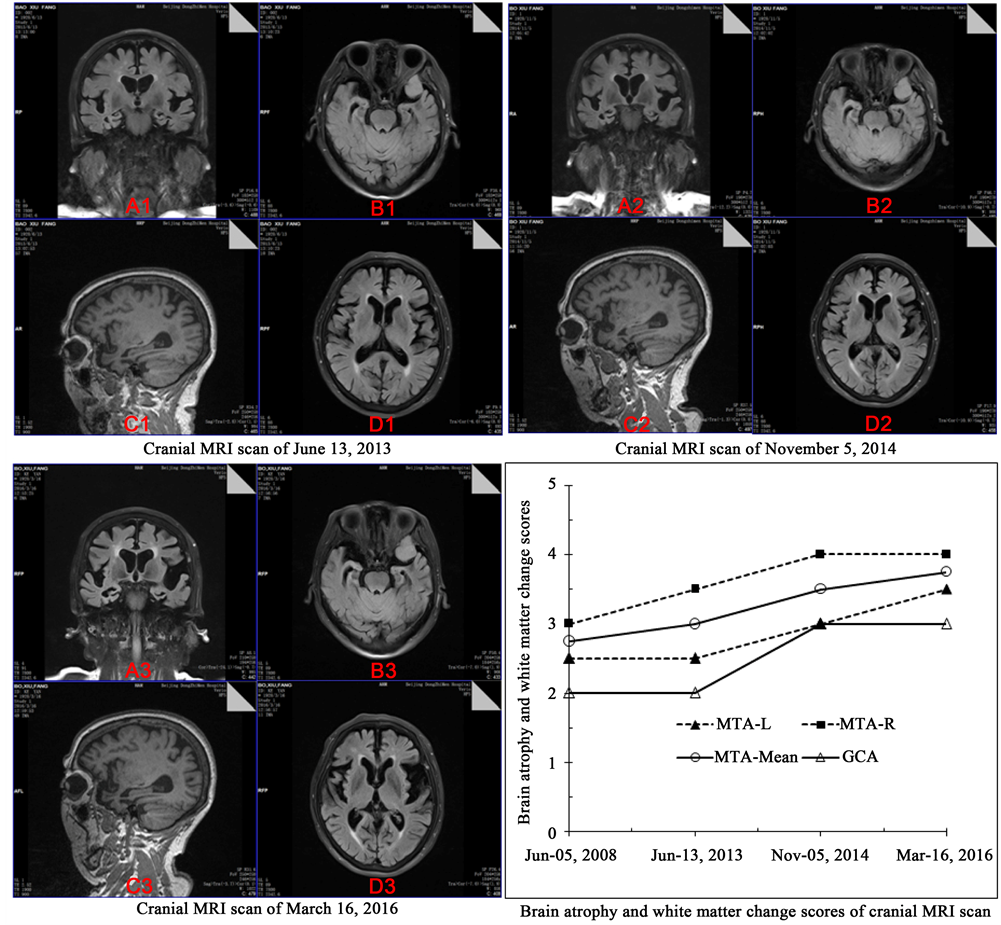

Figure 1. Brain atrophy and white matter changes of cranial MRI scan. Note: (A), Coronal FLAIR, MTA scale was assessed; (B) Axial FLAIR; (C) Sagittal T1 image, GCA scales was assessed; (D) Axial FLAIR. There was obvious increase of MTA scale and GCA scale, from June 5, 2008 to March 16, 2016. However, there are no significant aggravation of the white matter demyelination and lacunar infarction.

With carefully evaluation, she was diagnosed as mild dementia due to Alzheimer’s disease. The diagnosis was given by the following criteria, First, the patient was brought to our memory clinic for her insidious and progressive cognitive decline in half year without fluctuating characteristics. Second, she has more than two domains of cognitive impairment measured by global cognitive disorder with MMSE adjusted by education, ≤22 for primary school, and the cognitive impairment has interfered with her daily activities [3] [4] . Third, her brain MRI scan showed severe atrophy of the bilateral hippocampal volume, with an age-adjusted MTA-scale abnormal score 3 or more for 75 years and more. Overall, this is quite accord with AD diagnostic criteria [5] [6] [7] . Other diseases that may cause cognitive impairment were excluded by the patient’s negative results of laboratory tests.